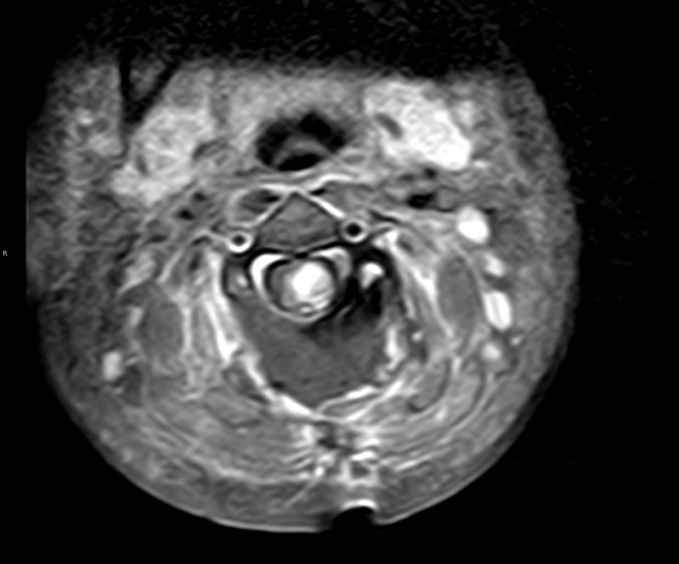

术前MRI提示C3-4髓内占位并破裂出血

术后MR复查结果